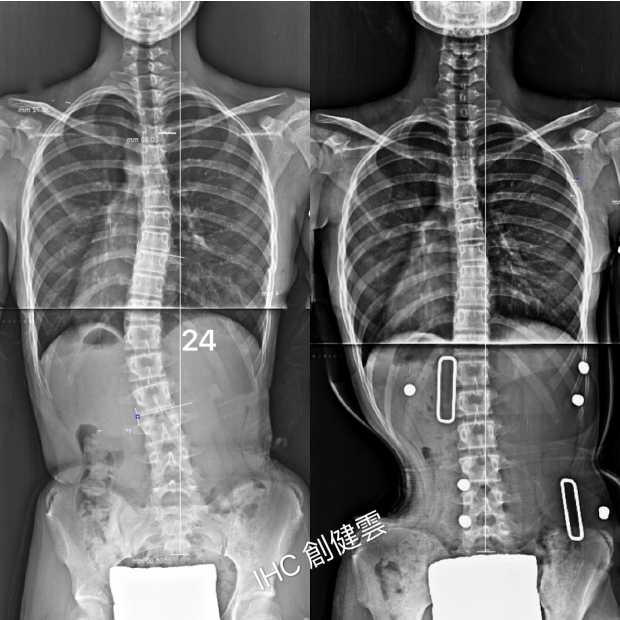

13歲S型脊椎側彎女孩

胸椎39度,腰椎36度